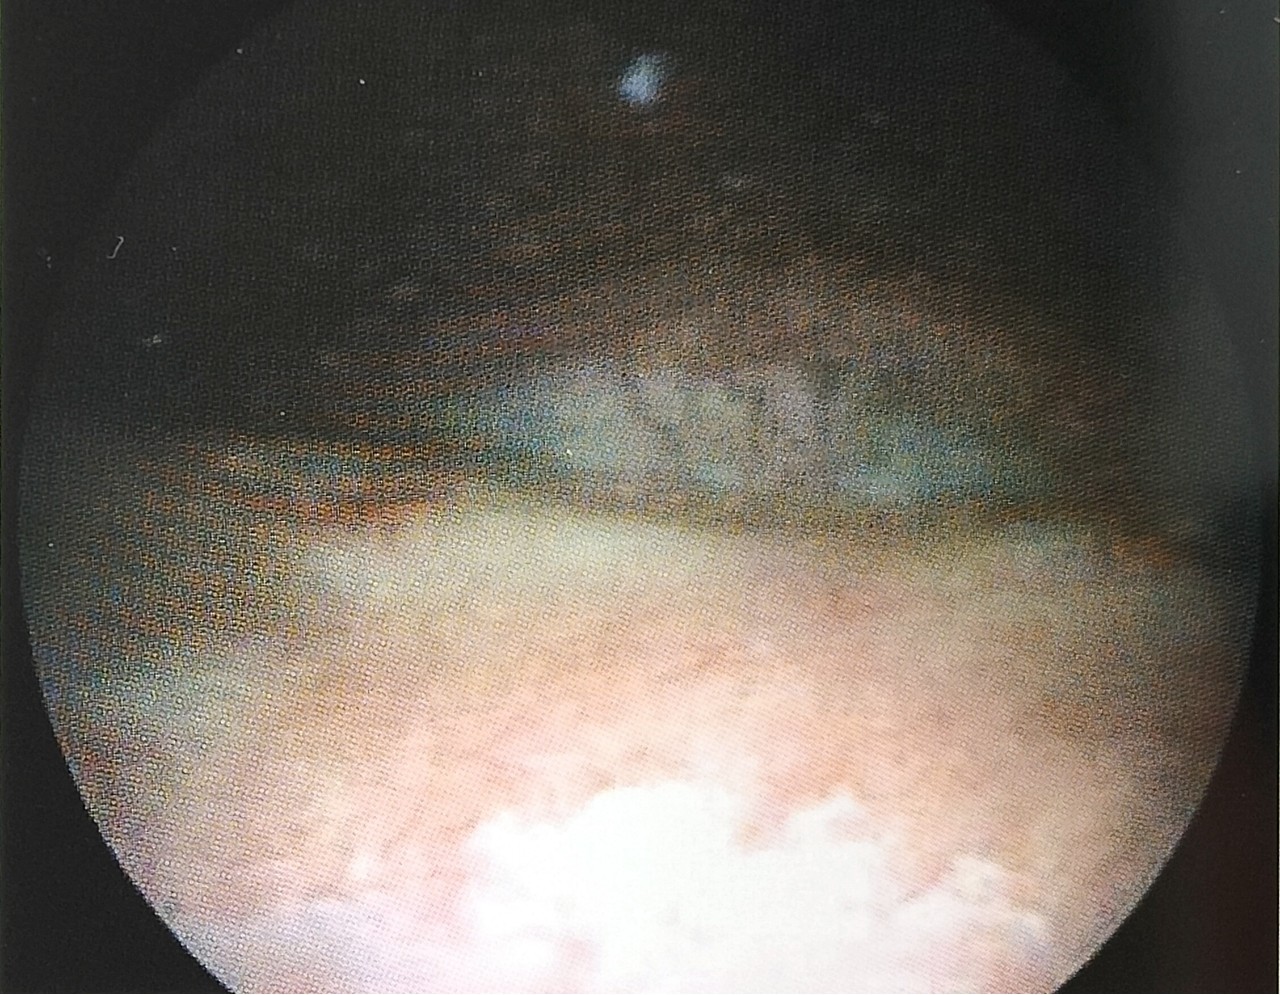

在慢性刺激或感染的作用下,膀胱移行上皮组织转化为鳞状上皮,表层角化,并有角化蛋白形成,被认为是癌前病变。膀胱镜下的大体病理改变:膀胱内壁可见灰白或灰色斑状隆起,大小不等,单发或多发。病变主要位于膀胱三角区及膀胱颈部(图1、图2)。病理分三种类型:充血型、斑点型、薄斑型、厚斑型。典型的镜检可见“飘雪征”,是大量脱落的上皮及角质碎片在水中游动,呈现暴雪景象。

(图1)

(图2)